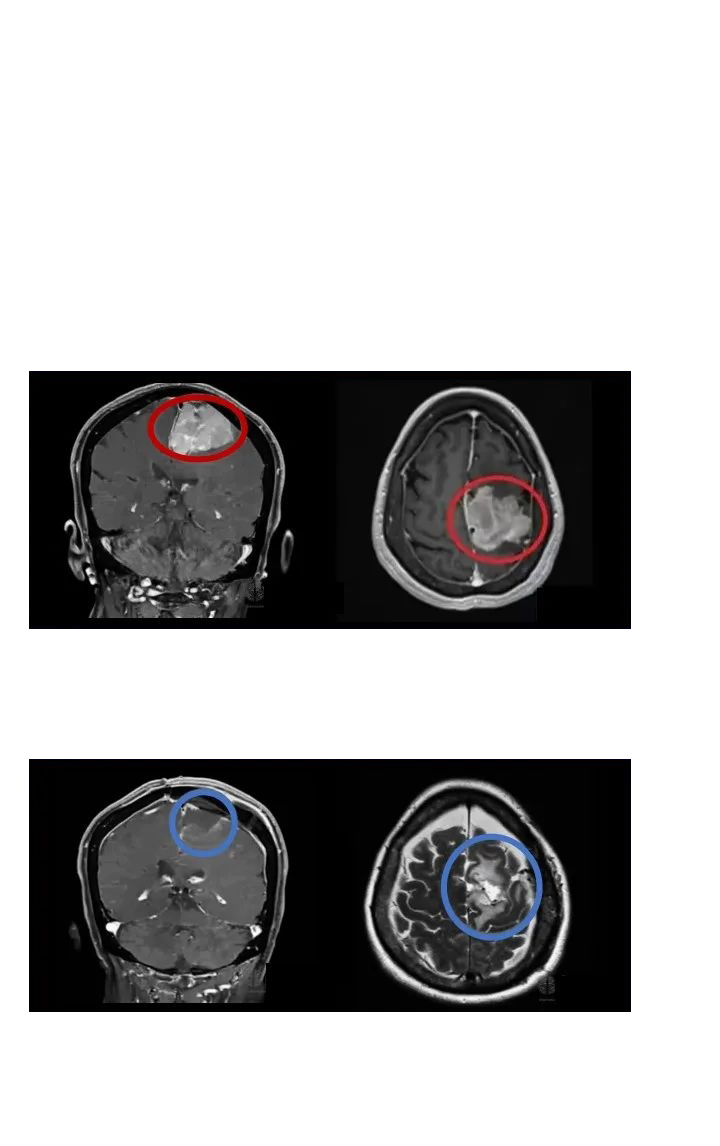

首刀、伽马刀后脑膜瘤多发恶化,INC巴教授Simpson 1级全切术,4年没有复发

一次手术只实施了部分切除。

二年病变复发,他接受了伽玛刀治疗,

三年病变竟然恶化成了多发性脑膜瘤。

较大脑膜瘤长在大静脉窦、大脑镰旁,INC巴教授手术全切,没有复发、无后遗症

2012年王女士体检时查出左侧额部大脑镰旁脑膜瘤,考虑肿瘤为良性,

自身年纪也比较大,就听取了医生的保守治疗建议。

但随着肿瘤生长,头痛愈发严重,吃止痛药、试用民间秘方都毫无效果。